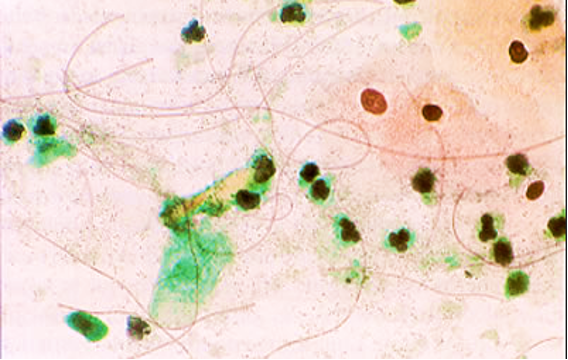

Figs 1 and 2 from a mass in the right hypochondriac region.

Make your diagnosis.

Fig 1 : Giemsa x 100

Fig 2 : Giemsa x 400